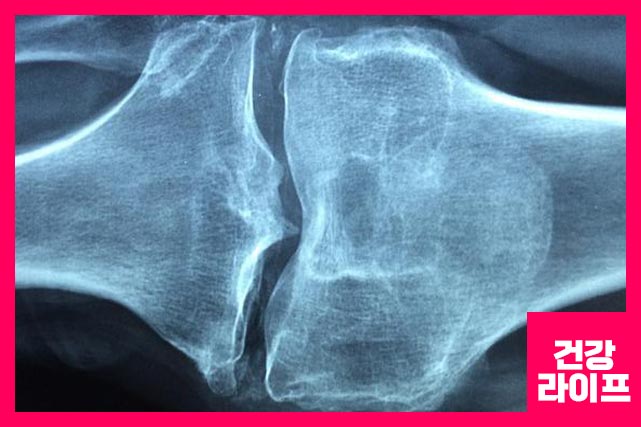

1. 골관절염

퇴행성 관절염이라고도 하는 골관절염이 있습니다. 무릎의 연골을 나이가 들면서 많이 사용하고 마모가 되면서 통증까지 생기게 합니다.

패혈성 관절염은 발열과 함께 발생하며 통증이 시작되기 전에는 특별한 외상 증상이 나타나지 않습니다. 패혈성 관절염은 매우 빠른 속도로 무릎 연골을 손상시킬 수 있습니다.